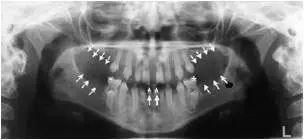

然而对有些孩子来讲,换牙之路真的就太不顺利了。不但乳牙没有按时脱落,而且恒牙也迟迟不肯露面。家长本想去医院寻求一个解决办法,得到的却是令人猝不及防的真相——孩子的X线片(全景片)清晰地显示,颌骨里竟然少了几颗牙齿。

箭头所示为双侧上颌侧切牙缺失